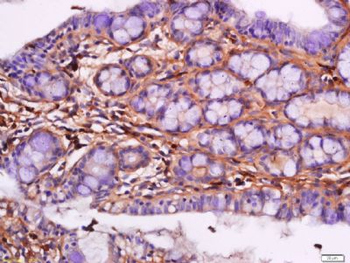

50 μl, 100 μl, 200 μlTIG2 Rabbit Polyclonal Antibody [orb11481]

IF, IHC-Fr, IHC-P

Human, Mouse, Rabbit

Human, Mouse, Rabbit, Rat

Rabbit

Polyclonal

Unconjugated

50 μl, 100 μl, 200 μlAnti-Aurora A/AURKA Antibody [orb1290027]